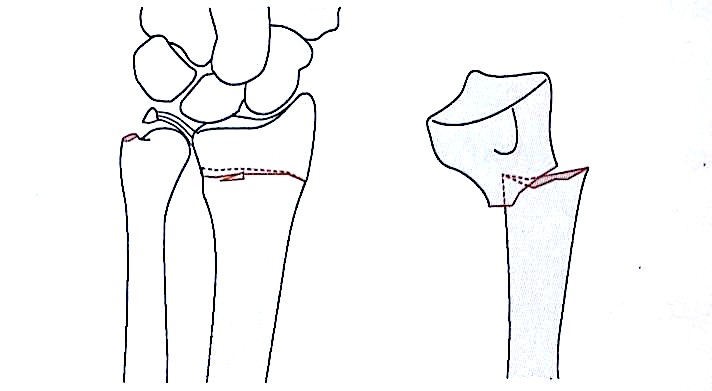

Метафизарный перелом сгибания типа I

Суставной и сдвиг типа II

Сжатие сжатия типа III поверхности суставной поверхности

Авульсивный перелом Avulsion типа IV, вывих, вывих

Смешанные переломы типа V (переломы с высокой энергией авульсии)